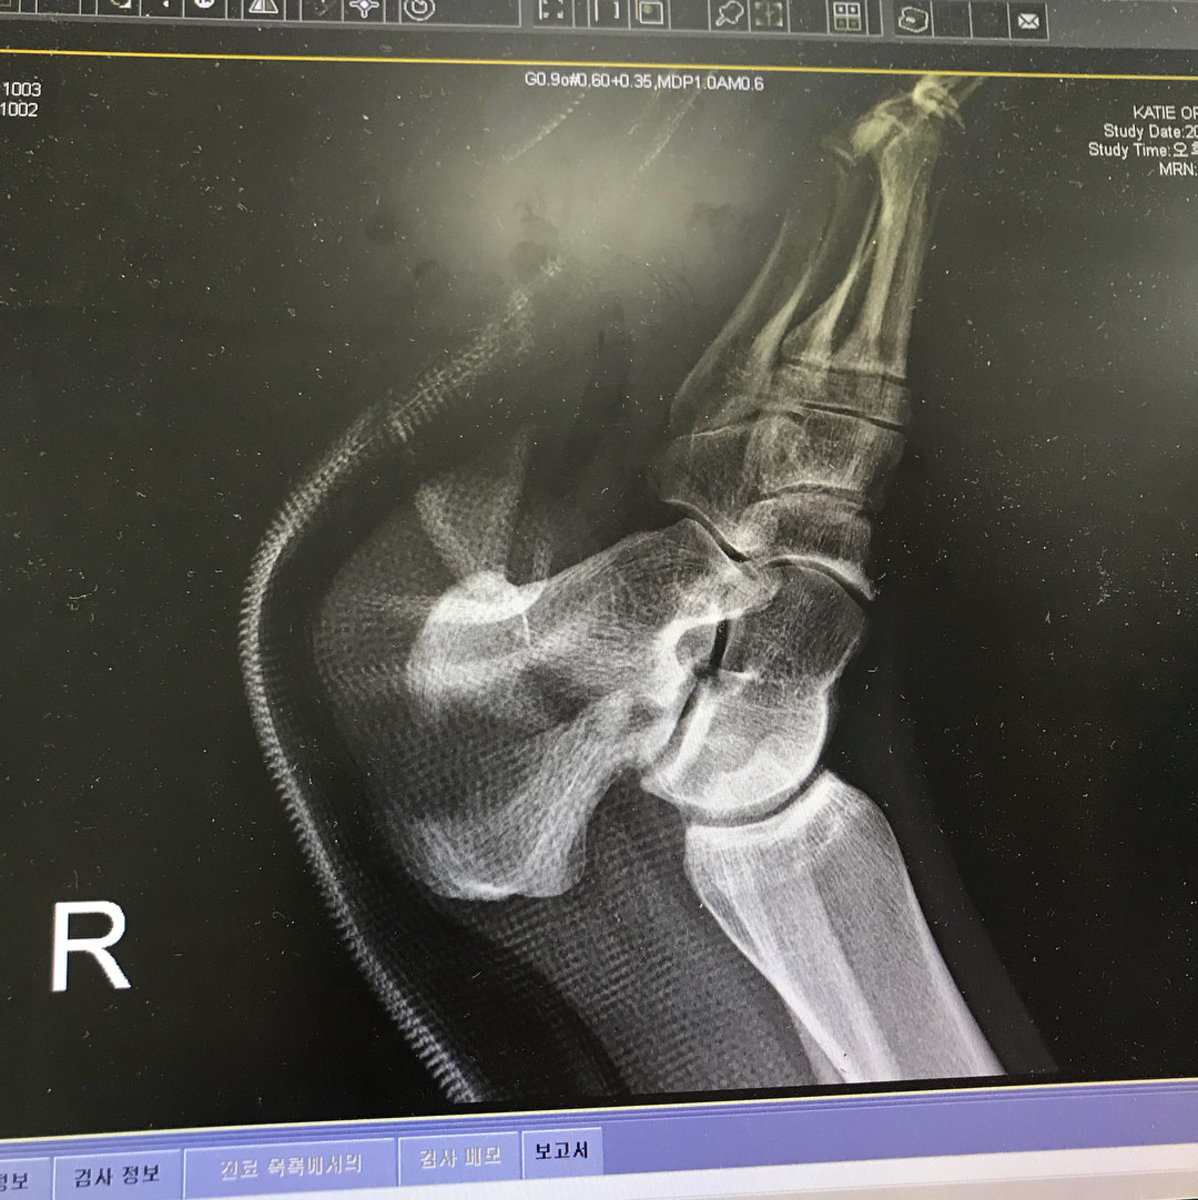

The British Olympic Association (BOA) said in a statement that the 20-year-old had suffered a severe fracture to her right heel bone in a fall on Thursday and would undergo emergency surgery.

Ormerod posted a photograph of herself in a cast before the surgery on her Instagram page.